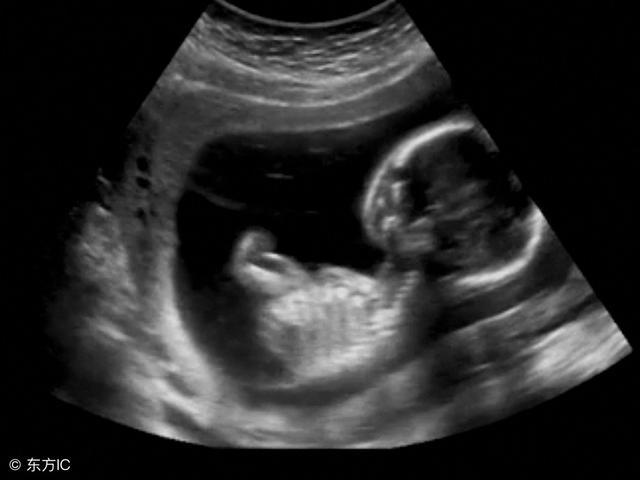

超声下盆腔显影是不孕不育诊疗过程中的一项检查技术,通过向宫腔、盆腔内注入一定量的“造影剂”,使子宫、输卵管等盆腔内器官在超声下的影像更为清晰,从而提高超声检查的准确性,同时通过动态观察“造影剂”在输卵管内的流通情况,而对输卵管的通畅性进行判断。可用于宫腔内占位、宫腔粘连、生殖道畸形、盆腔粘连及输卵管是否通畅的检查,为临床诊断提供依据。

目前,超声下盆腔显影术主要用于不孕症和习惯性流产的原因检查,超声显影能发现良性内膜息肉、宫腔粘连等阻碍妊娠的原因。习惯性流产可能由于宫腔内纤维隔或宫腔形态异常所致。这些做普通超声难以发现,但是在超声显影术中就变得清楚了。在不孕症的检查中,如果女方监测排卵是正常的,男方精液检查也是正常的,医生就会建议患者检查输卵管是否通畅,这时就可以进行超声下盆腔显影检查了。